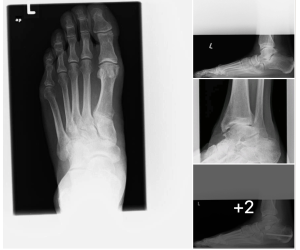

Correcting MIS Lapidus

Dr. Kris Di Nucci

MIS surgeons — here is a patient who presents 10 months after an MIS Lapidus arthrodesis. She reports recurrence of her bunion and mild sesamoid...